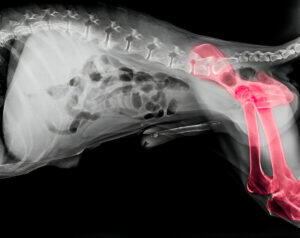

Gun dogs happen to have a lot of knee and joint injuries due to their hunting and working nature. The reports suggest that working and gun dogs are likely to be 60% more prone to have a cruciate injury. However, training gun dogs can reduce these medical problems.

Cruciate Ligament Rupture

This is a common injury that gun dogs happen to experience due to their work. Musculoskeletal injuries are especially common in larger breeds, resulting in knee joint instability.

The treatment of this rupture may vary. It could start from conservative management, such as rest physiotherapy, to surgical interventions like tibial plateau leveling osteotomy (TPLO). The intensity of the rupture plays a crucial role in the final treatment option.

Hip Dysplasia

The next condition is Hip Dysplasia a hereditary condition that affects the hip joint, often leading to pain. This also causes lameness in dogs, eventually leading them to have arthritis.

Managing Hip Dysplasia

Hip dysplasia is tried to manage well before going for treatment, which could be in severe cases. The veterinarians can train the parents to consider the following.

Moreover, severe cases may call for surgical intervention.

Elbow Dysplasia

Elbow dysplasia can indicate the development of abnormalities affecting the elbow joint, causing pain and lameness.

Treatment

The treatment of elbow dysplasia ranges from conservative management to surgical procedures depending on the intensity of the abnormalities developed.

It is important to mention here that these musculoskeletal injuries often make the gun dogs have unspecific lameness. They could feel sluggish and limp, showing no interest in running or their hunting activities. Therefore, gun dog nutrition is crucial to monitor and care for the do to excel in his work.